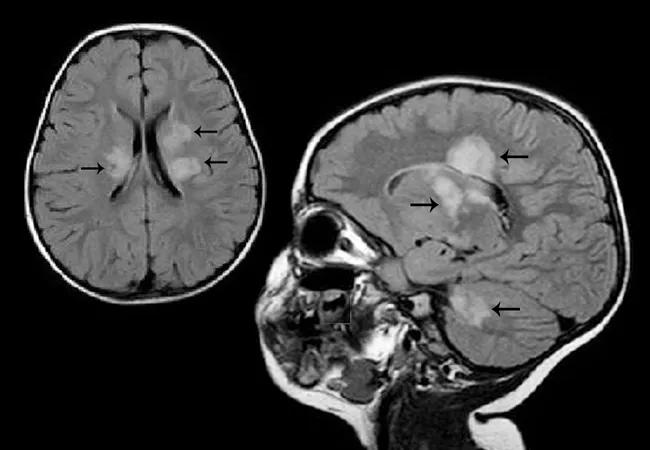

Many findings from this patient sample were consistent with prior reports of POMS, including general findings in terms of presenting symptoms, MRI findings and laboratory test results. Notable specific findings that confirmed previous literature reports of POMS included: